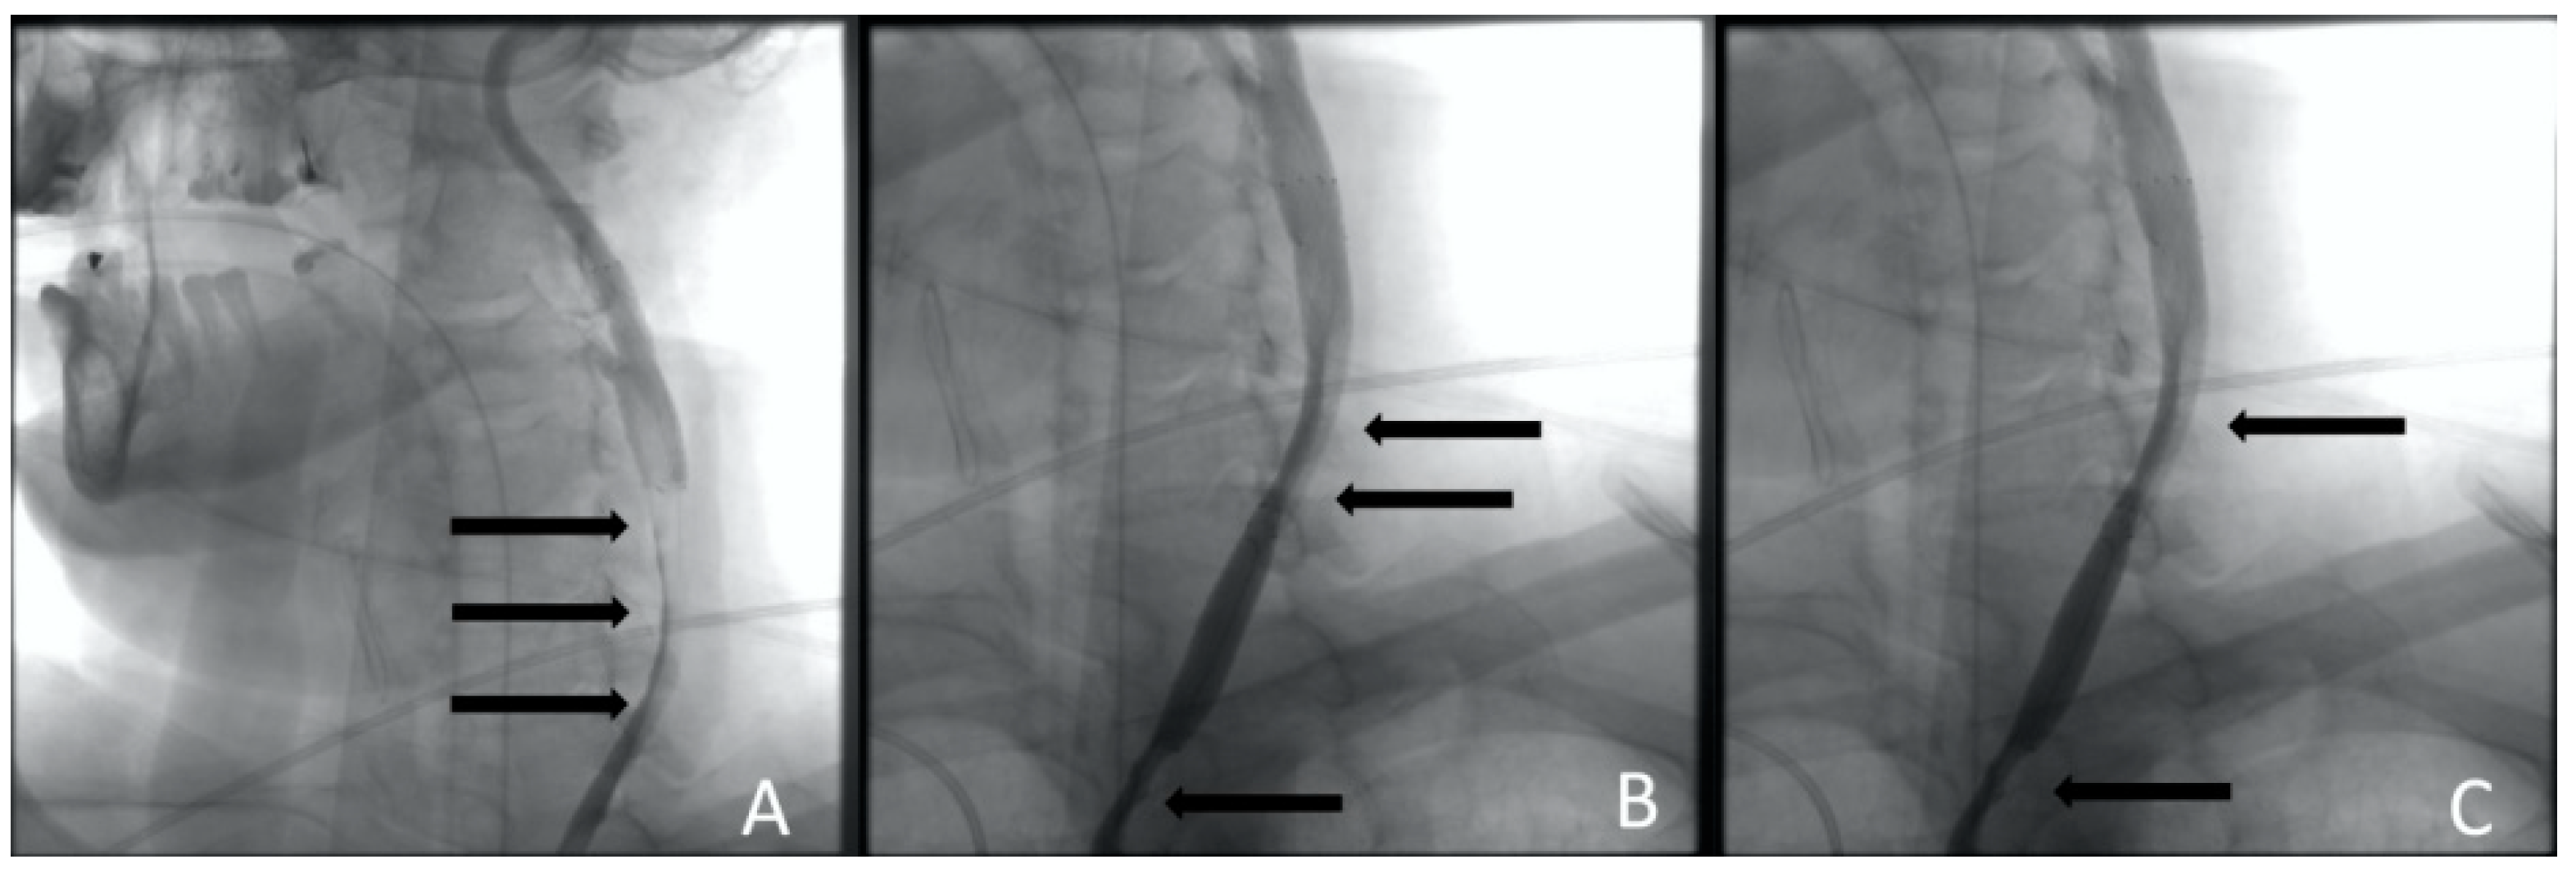

Figure 4.

Clinical Case 1, Patient M., 73 years old. Results of the angiography: (A) brachiocephalic and subclavian artery angiography via radial access; (B) left common carotid artery angiography, a low contrast defect is visible throughout; (C) left subclavian angiography. A contrast defect is visible throughout the artery.

After the emergency examination by the cardiac surgeon and neurologist, a decision of carotid revascularization and stenting was performed. Through the right common femoral artery, with no technical difficulties, the revascularization of the left common carotid artery (CCA) by the implantation of three self-expending carotid stents into the left internal carotid artery (ICA) and CCA was performed (Figure 5).

Figure 5.

Clinical Case 1, Patient M., 73 years old. Results of the angiography: (A) left ICA stenting with the first stent; (B) CCA stenting with a second stent; (C) CCA stenting with the third stent. The arrows indicate contrast defects that persist after stenting (compression of the true lumen).